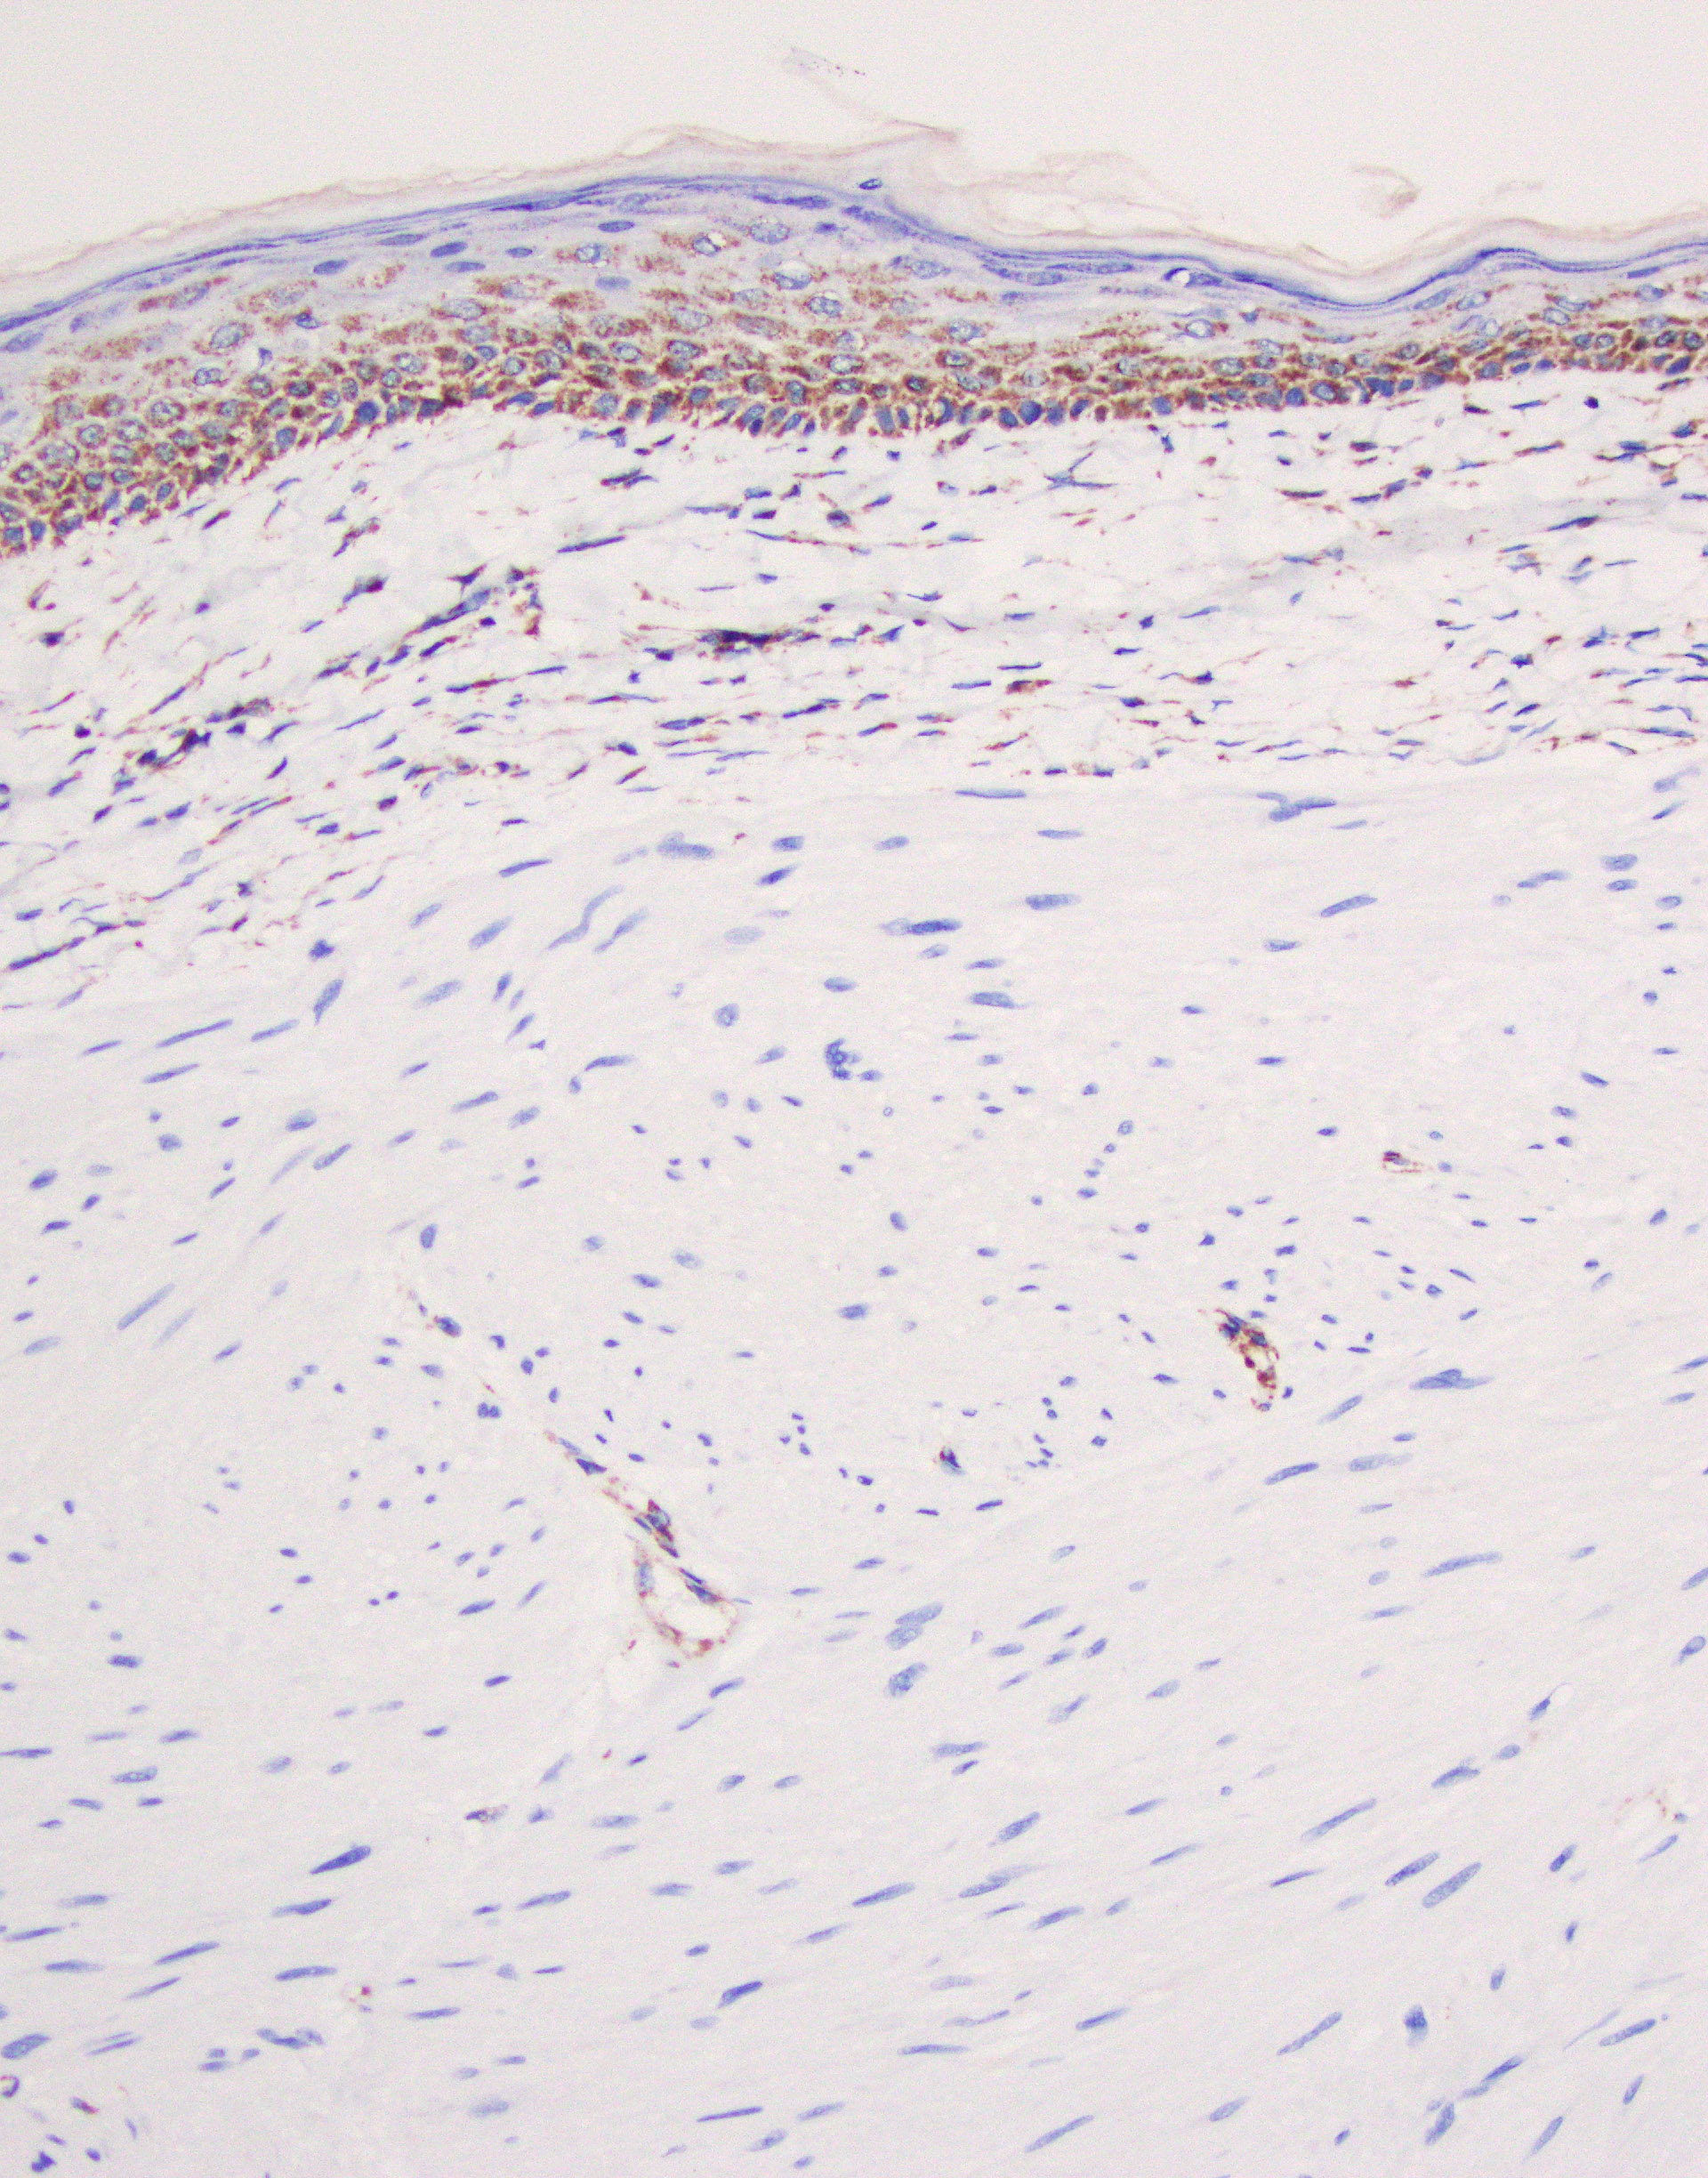

The patient is showing well-circumscribed (Fig 1) leiomyomatous lesions with features of the Hereditary Leiomyomatosis and Renal Cell Cancer (HLRCC) Syndrome (OMIM 150800, AKA Reed’s syndrome) which is produced due to germline mutations of the gene coding for the mitochondrial enzyme Fumarate Hydratase (FH, 1q43). This syndrome is characterized by multiple cutaneous, and in women uterine, leiomyomas exhibiting some distinctive features seen in this particular lesion; mainly cytoplasmic eosinophilic globules (Figure 2), nuclei with powdery chromatin exhibiting prominent nucleoli (Figure 3). Uterine examples tend to show similar albeit more pronounced nuclear features in addition to Hemangiopericytoma-like (HPC-like) vasculature, nuclear periodicity among other unique characteristics. Likewise, renal cell carcinomas arising in the context of HLRCC have their own set of distinct features including similar powdery chromatin and large nuclei with viral-like macronucleoli. These renal tumors were historically classified as type II papillary renal cell carcinomas (RCCs) or unclassifiable RCCs. The absence of the normal enzyme can be demonstrated by immunohistochemistry for Fumarate Hydratase (FH), which will show loss of staining in the lesional cells like in our case (Fig 4). In addition, one could performed immunohistochemistry for the abnormal product of the mutated FH gene (2-Succinocysteine, 2SC) a test that is not widely available.